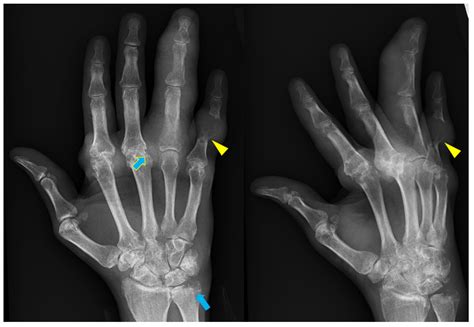

• Arthritis: Hand X Ray can reveal the characteristic bone changes associated with different types of arthritis, such as rheumatoid arthritis and osteoarthritis.

Interpreting Hand X Ray results requires a trained eye. Radiologists and orthopedic specialists are typically responsible for analyzing the images. Key areas of focus include:

• Bone Density: Variations in bone density can indicate fractures, tumors, or other abnormalities.

• Joint Spaces: Narrowing of joint spaces can be a sign of arthritis.

• Soft Tissue: While X-rays primarily focus on bones, they can also provide some information about soft tissues, such as swelling or the presence of foreign bodies.